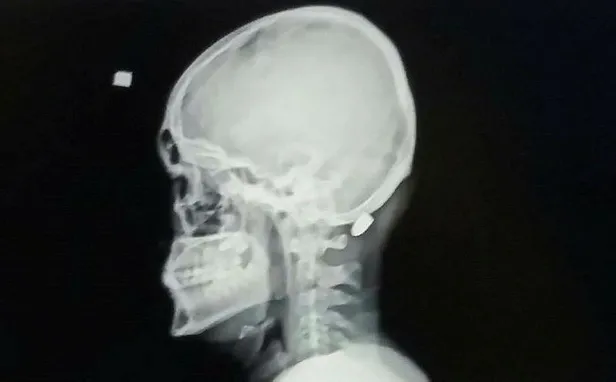

Trabzon'un Vakfıkebir ilçesindeki Karadağ Yaylası'nda önceki gün saat 14.00 sıralarında babası ve amcası ile birlikte yaylada bir evin dış cephe kaplamasını yapan 18 yaşındaki Ali Kuleyin'in başına nerden atıldığı belli olmayan kurşun isabet etti. İlk önce kurşun olduğunu anlamayan genç, elini başına götürdüğünde kan geldiğini anlayınca ailesine haber verdi. Ailesi tarafından Vakfıkebir Devlet Hastanesi kaldırılan gence isabet eden yorgun mermi başarılı bir operasyonla saplandığı yerden çıkartıldı. Tedavisinin ardından taburcu edilen Kuleyin'in başına isabet eden merminin hangi tabancadan çıktığının belirlenmesi için balistik incelenmeye gönderildi.

Kurşun hiçbir zaman havada kalmıyor bu yere inecek. Bugün benim çocuğuma düştü yarın belki o silahı atanın çocuğuna da düşebilir. Duyarlı olsunlar. Biz buna karşıyız. Benim çocuğum bugün ölmüş olabilirdi. Mermi bir santim daha aşağıya inmiş olsaydı felç kalabilirmiş. Allah korudu. Kurşun yorgun olduğu için fazla etki yapmadı. Biz bugün belki de cenaze işleri ile uğraşıyorduk. Ben her zaman oğluma kafana akıl koy diyordum, o gitti kafasına kurşun koydu" diye konuştu.